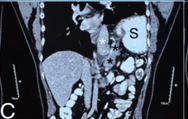

Congenital diaphragmatic hernia (CDH) is a birth defect involving improper formation of the diaphragm, leading to the protrusion of abdominal organs into the chest cavity. The CDH is classified depending on the location of the defect as postero-lateral, central and anterior. Depending on the side, it is classified as right, left and bilateral. A majority of CDH defects are postero-lateral defects and are commonly referred to as Bochdalek hernias (BH). Herein, the authors present the case of a 29 years old male patient diagnosed with a large left recurrent Bochdalek hernia. He was operated for it in another hospital by another surgeon 5 months back. That previous surgical intervention was initially planned via laparoscopy. But, intraoperatively, it had to be converted to open surgery due to technical difficulty. Post the first surgery, after about 1.5 months, he started developing pain in the back of his left chest. However, due to financial constraints, he did not seek any consultation with anyone at that time. The authors successfully performed a laparoscopic repair of this difficult condition. The rationale for reporting this case is to underscore the relative ease of a laparoscopic over open surgical intervention, on the ‘roof’ of the abdomen and also the lower chest. Also, it hopes to highlight that laparoscopic repair of BH is feasible even in challenging, difficult and recurrent scenarios, in an advanced setup backed up by the requisite surgical expertise.